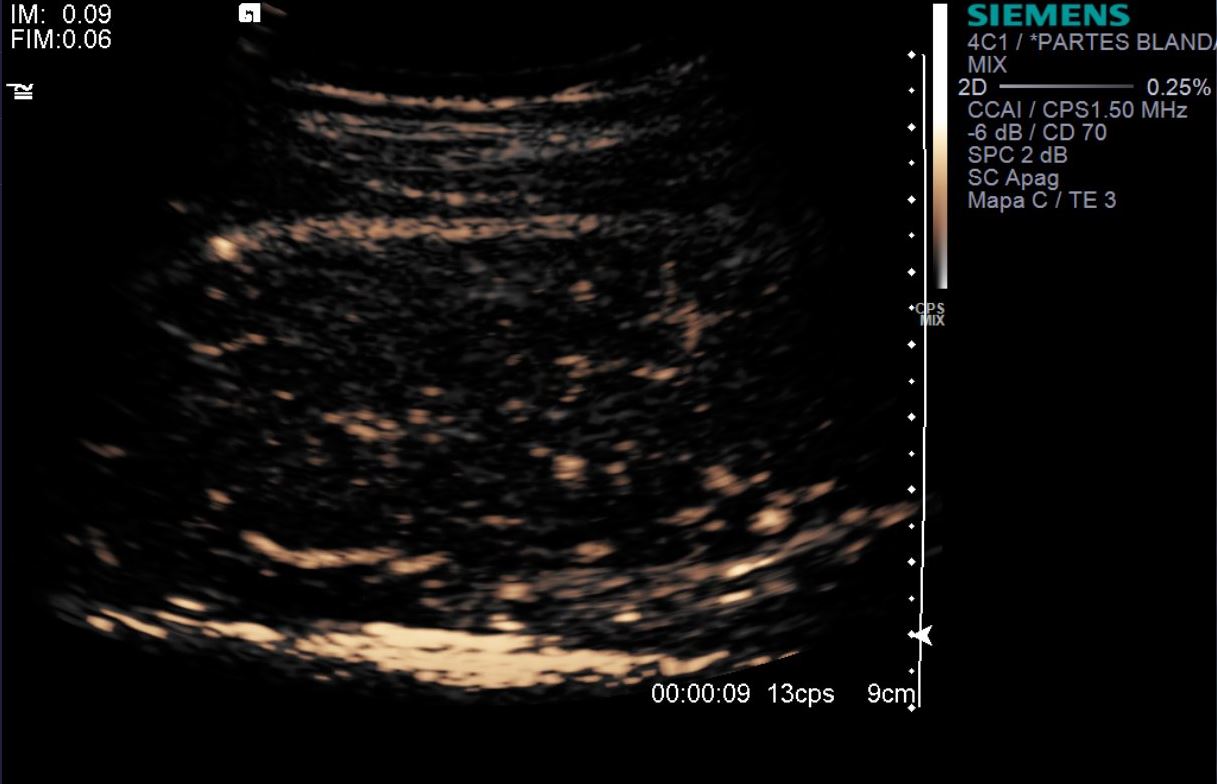

eco con contraste IV